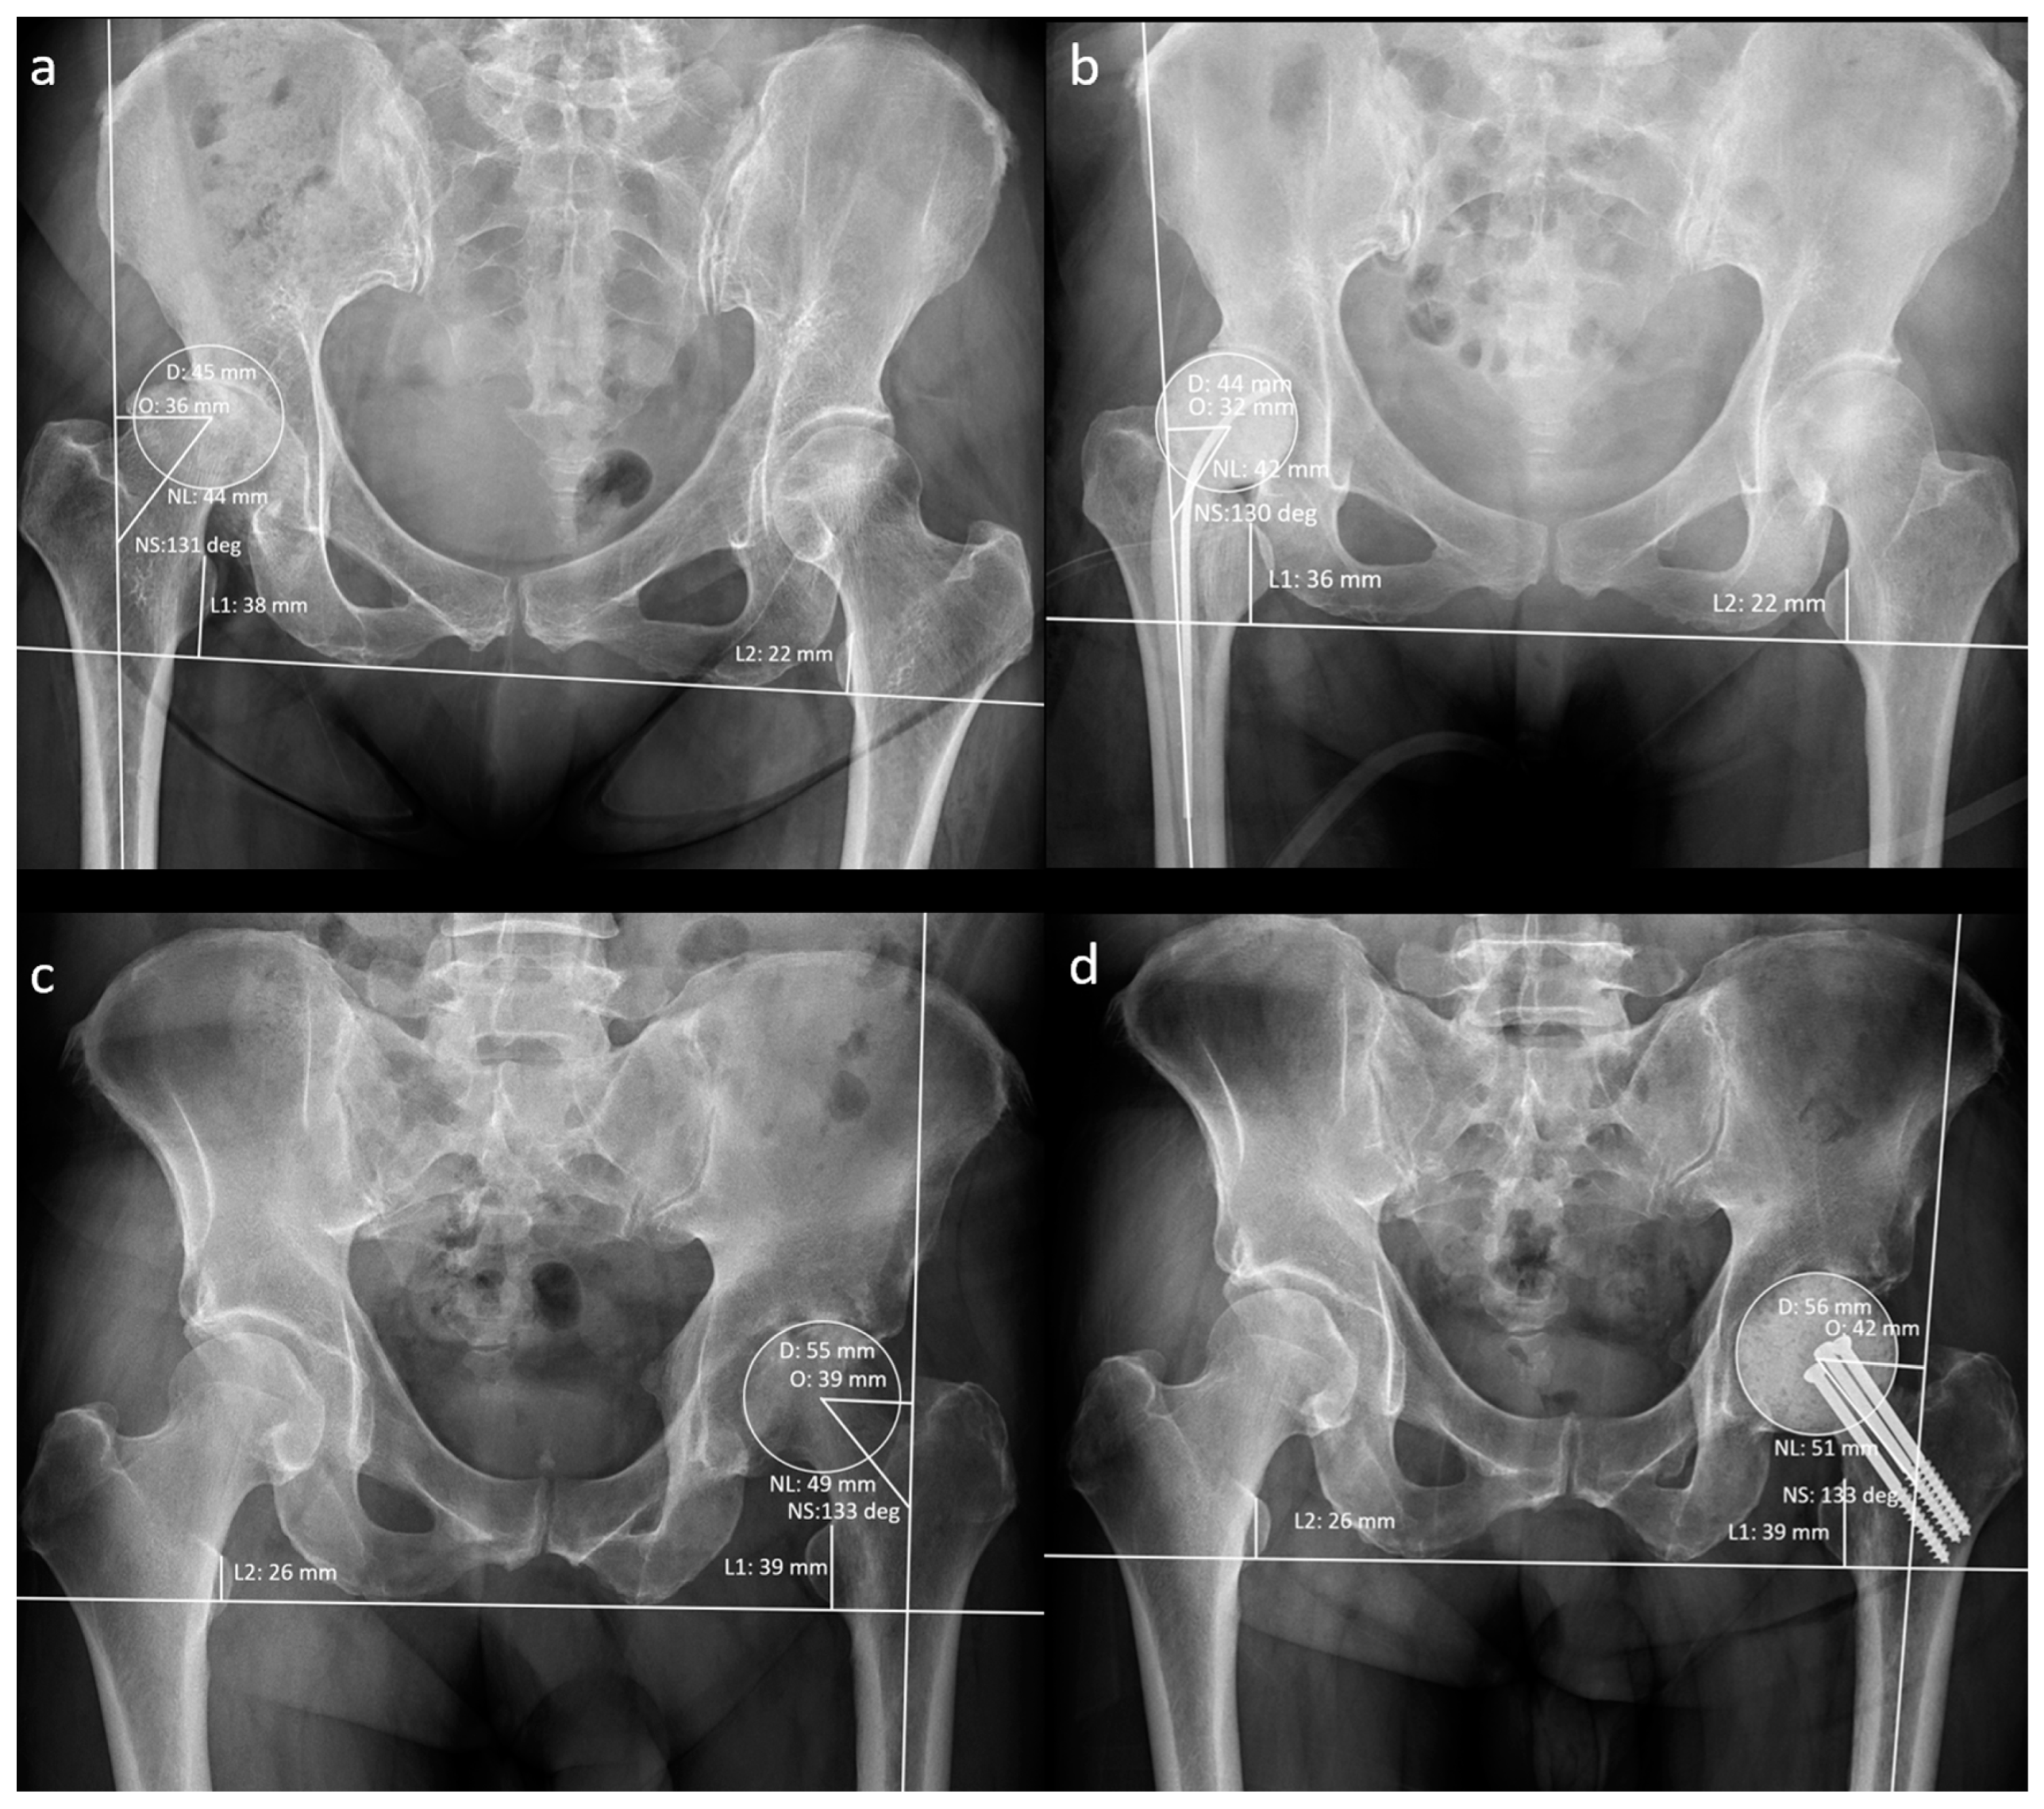

Figure 3.

Measurement of radiographic hip geometrical parameters. (a) Pre-operative n-MS hip, (b) post-operative n-MS hip, (c) pre-operative MS hip, and (d) post-operative MS hip. Δhip parameters: femoral head diameter difference (post-operative D–pre-operative D), femoral neck length difference (post-operative NL–pre-operative NL), neck–shaft angle difference (post-operative NS–preoperative NS), femoral offset difference (post-operative O–pre-operative O), and leg-length discrepancy difference (post-operative L1–L2)–(pre-operative L1–L2).